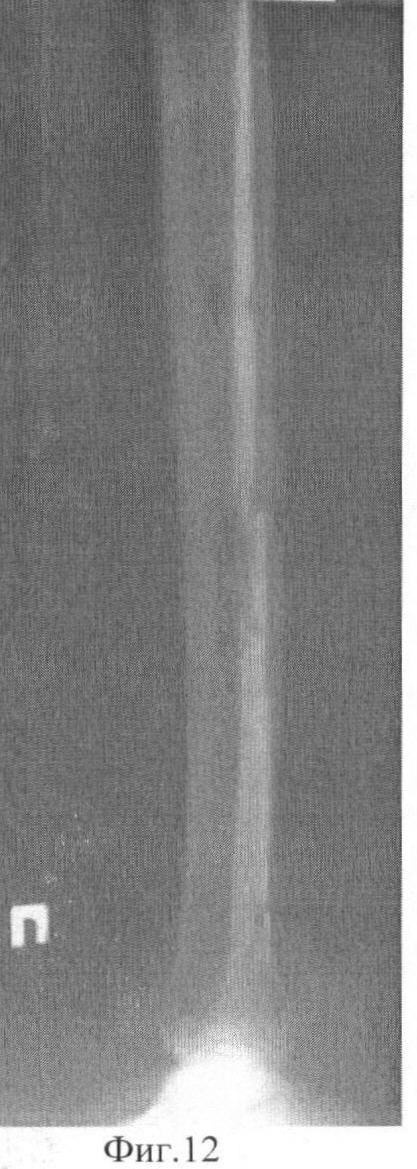

Фиг.12 Фоторентгенограммы больного после снятия аппарата внешней фиксации: боковая проекция;

Демонстрируем сказанное клиническим наблюдением. Больной С-ов, 18 лет, история болезни 12608/2008. В результате ДТП получил оскольчатый перелом средней трети обеих костей правой голени со смещением фрагментов (Фиг.5 и 6). Выполнен чрескостный остеосинтез аппаратом внешней фиксации. Вначале были проведены базовые чрескостные элементы и смонтирована рама аппарата (Фиг.1). Затем смещение фрагментов было устранено с помощью стержней-шурупов (Фиг.2). При этом возникли деформация и напряжение базовых чрескостных элементов. Были введены стабилизирующие стержни-шурупы (Фиг.3). После этого, не опасаясь вторичного смещения фрагментов, базовые чрескостные элементы были переустановлены (Фиг.7 и 8). Период фиксации составил 103 дня. Осложнений (вторичного смещения фрагментов, воспаления мягких тканей в области выхода чрескостных элементов) отмечено не было (Фиг.9 и 10). Через неделю после снятия аппарата внешней фиксации (Фиг.11-14) больной приступил к труду.